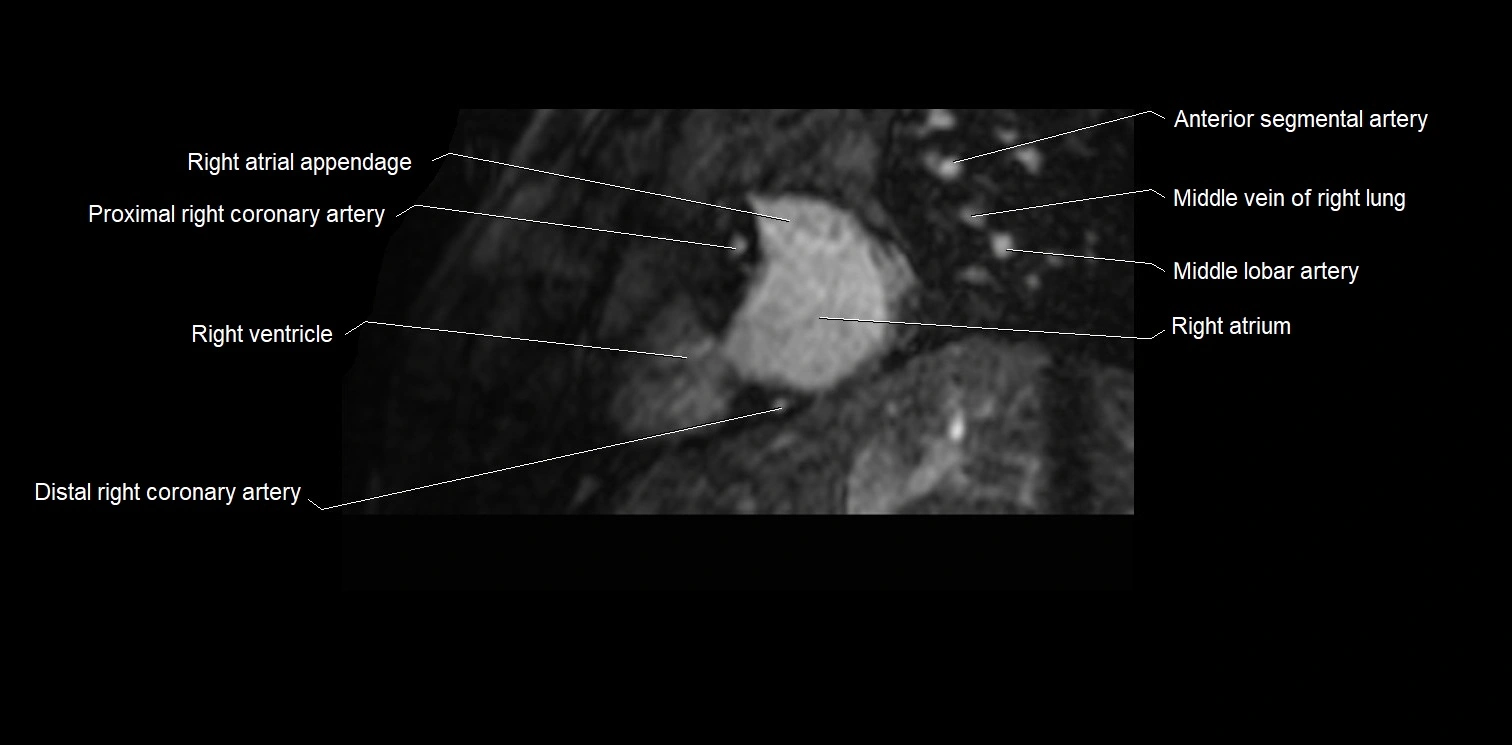

- Right atrium

- Right coronary artery (RCA)

- Right ventricle